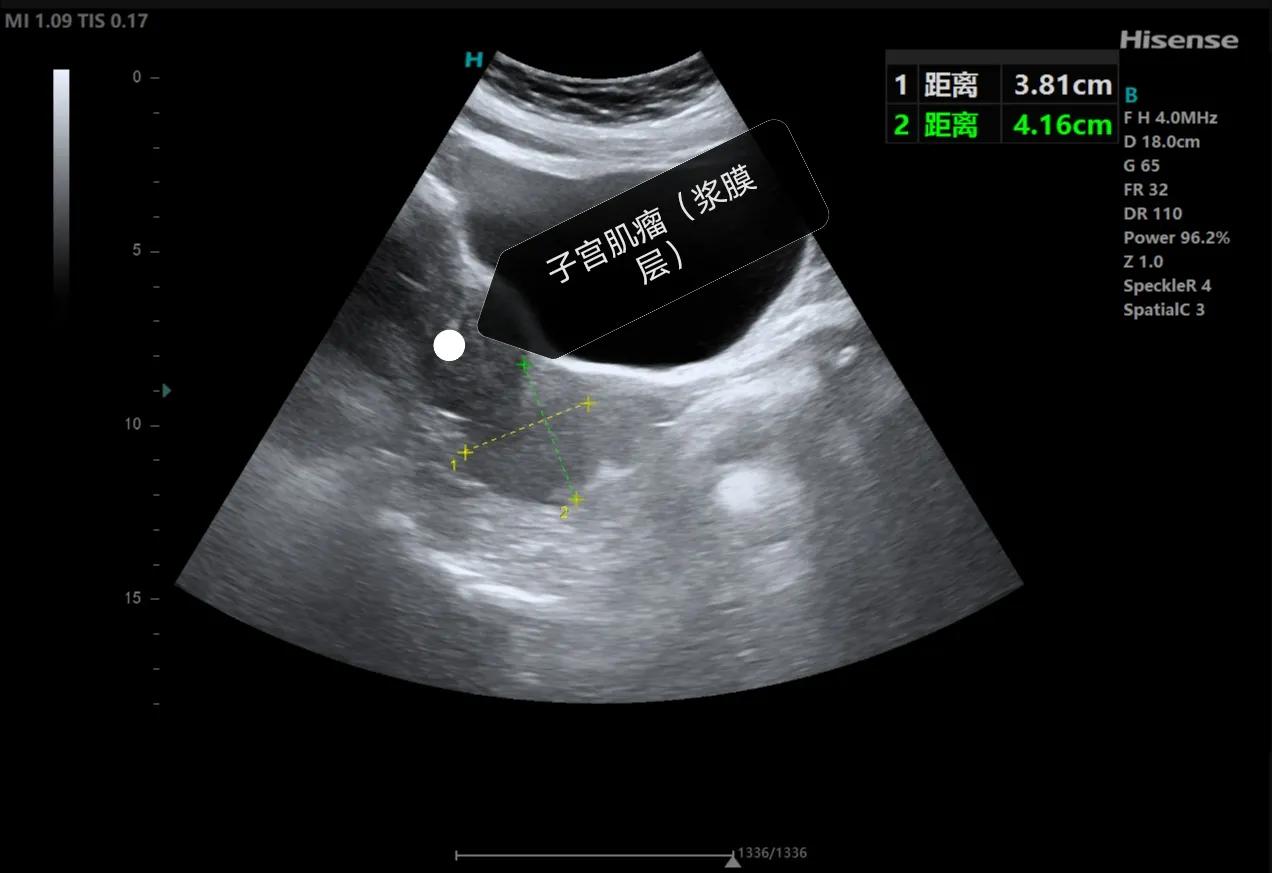

女性朋友关心的第二个问题“怎么确定自己有没有子宫肌瘤、肌瘤多大”,确定是不是患有子宫肌瘤很简单,做一个超声检查就可以了,下面我给大家分享一下子宫肌瘤的超声表现,子宫肌瘤根据位置分为粘膜下肌瘤、肌壁间肌瘤和浆膜层肌瘤,在超声上主要表现为低回声结节,边界比较清楚,小的肌瘤一般形态规则,呈椭圆形,大的肌瘤形态可表现为欠规则,呈分叶状,肌瘤周边一般可见环状的血流信号。

浆膜外肌瘤,肌瘤向外凸